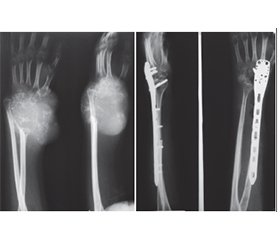

Актуальність. Гігантоклітинна пухлина (ГКП) дистального відділу променевої кістки є доброякісною, місцевоагресивною пухлиною, яка характеризується частими рецидивами та має певний метастатичний потенціал. Внутрішньокісткова або сегментарна резекція дистального відділу променевої кістки з ГКП створює дефект у дистальному відділі променевої кістки. Основними хірургічними методиками реконструкції такого дефекту є застосування спонгіозних ало-/автотрансплантатів, штучних матеріалів, поліметилметакрилату, васкуляризованих і неваскуляризованих кісткових автотрансплантатів, кістково-суглобових алотрансплантатів та індивідуальних ендопротезів. Ми проводили оцінку онкологічних, хірургічних і функціональних результатів при ГКП дистального відділу променевої кістки з урахуванням різних методик хірургічних втручань і реконструкцій. Мета: хірургічне видалення ГКП дистального відділу променевої кістки, зниження ймовірності рецидиву пухлини та збереження функції променево-зап’ясткового суглоба. Матеріали та методи. Проведено хірургічне лікування 21 хворого з ГКП дистального відділу променевої кістки. Середній вік хворих становив 28,7 року (діапазон від 18 до 39 років). Проліковано 8 (38,1 %) пацієнтів із ГКП II/III ступеня (за Кампаначчі) дистального відділу променевої кістки, після резекції дистального сегмента променевої кістки з пухлиною та реконструкції дефекту кістки за допомогою неваскуляризованого малогомілкового автотрансплантата проксимального відділу малогомілкової кістки, фіксованого за допомогою пластини або серкляжів до залишку променевої кістки. 7 (33,3 %) пацієнтам із ГКП I ступеня (за Кампаначчі) проведена внутрішньокісткова резекція дистального відділу променевої кістки з пухлиною та пластика дефекту кістки матеріалом на основі біоактивного скла (біокомпозитом) або спонгіозна автопластика. 1 (4,8 %) пацієнту з ГКП II ступеня (за Кампаначчі) та 2 (9,5 %) пацієнтам із рецидивом пухлини виконана внутрішньокісткова резекція дистального відділу променевої кістки з пухлиною та пластика дефекту поліметилметакрилатом (кістковим цементом), 2 (9,5 %) пацієнтам із ГКП III ступеня (за Кампаначчі) та 1 (4,8 %) пацієнту після повторних рецидивів пухлини виконано сегментарну резекцію кістки із заміщенням дефекту автотрансплантатом із проксимального відділу малогомілкової кістки й артродез у променево-зап’ястковому суглобі. Результати. Середній період спостереження становив 5,5 року (2,8–11,2 року). Унаслідок проведеного лікування у 3 (14,3 %) пацієнтів спостерігалися ускладнення — вивих автотрансплантата у променево-зап’ястковому суглобі при застосуванні неваскуляризованого малогомілкового автотрансплантата, вивих виправлено за рахунок повторного хірургічного втручання. Рецидиви пухлини спостерігалися у 3 (14,3 %) пацієнтів. У першому випадку після внутрішньокісткової резекції та пластики матеріалом на основі біоактивного скла виконано внутрішньокісткову резекцію, видалення матеріалу та пластику дефекту кістковим цементом, у другому — після внутрішньокісткової резекції та спонгіозної автопластики виконано внутрішньокісткову резекцію, видалення матеріалу та пластику дефекту кістковим цементом, у третьому — після внутрішньокісткової резекції та пластики кістковим цементом у зв’язку з повторним рецидивом пухлини виконано резекцію дистального сегмента променевої кістки з рецидивом пухлини й артродез у променево-зап’ястковому суглобі за допомогою автотрансплантата та металоостеосинтезу пластиною. Функціональні результати верхньої кінцівки після органозберігаючих операцій із приводу ГКП дистального відділу променевої кістки за шкалою MSTS становили в середньому: після внутрішньокісткової резекції та пластики матеріалом на основі біоактивного скла або спонгіозної автопластики — 98,52 % (97,7–99,9 %), після резекції дистального сегмента променевої кістки з пухлиною та реконструкції дефекту кістки за допомогою неваскуляризованого малогомілкового автотрансплантата — 89,34 % (78,6–92,5 %). Функціональні результати кінцівки оцінені у 21 пацієнта, відмінні результати отримані у 5 (23,8 %) пацієнтів, добрі — у 10 (47,6 %), задовільні — у 6 (28,6 %). Середній час зрощення у малогомілково-променевому з’єднанні після застосування неваскуляризованого малогомілкового автотрансплантата становив 7,5 місяця (3,2–16,1 місяця). Середня сила хвату прооперованої верхньої кінцівки після застосування неваскуляризованого малогомілкового автотрансплантата від нормальної сторони становила 50 % (35–69 %), а фактичне середнє значення для прооперованої сторони — 15 кг порівняно з 30 кг для протилежної нормальної сторони. Середній діапазон рухів становив: супінація передпліччя — 47° (31–69°), пронація передпліччя — 33° (16–55°), згинання кисті у долонний бік — 40° (18–67°), розгинання кисті (у тильний бік) — 29° (11–52°), при комбінованих рухах — 151° (75–180°). Загалом 59 % (24–70 %) комбінованого діапазону рухів було збережено у прооперованої сторони порівняно з протилежною нормальною стороною. 85,7 % прооперованих пацієнтів були задоволені результатами лікування. Висновки. Внутрішньокісткова резекція дистального відділу променевої кістки з пухлиною та пластика дефекту різними пластичними матеріалами є методикою вибору при ГКП I ступеня. Резекція дистального сегмента променевої кістки з пухлиною й автопластика дефекту кістки за допомогою проксимального сегмента неваскуляризованої малогомілкової кістки є ефективною методикою при ГКП II/III ступеня. Внутрішньокісткова резекція дистального відділу променевої кістки з пухлиною та пластика дефекту поліметилметакрилатом (кістковим цементом) є методикою вибору при рецидиві ГКП. Артродез у променево-зап’ястковому суглобі за допомогою автотрансплантата та металоостеосинтез пластиною є також методикою вибору при повторних рецидивах ГКП. Рецидив пухлини пов’язуємо з абластичним і радикальним видаленням ГКП. Ускладнення після органозберігаючих операцій із приводу ГКП дистального відділу променевої кістки пов’язуємо з недодержанням пацієнтами рекомендацій у післяопераційний період.

Background. Giant cell tumour (GCT) of the distal radius is a benign, locally aggressive bone tumour characterized by frequent recurrences and certain metastatic potential. Intramedullary or segmental resection of the distal radius affected by GCT results in a defect in the distal radial segment. Main surgical reconstruction techniques for such defects include the use of spongy allo- and autografts, synthetic materials, polymethylmethacrylate, vascularized and non-vascularized bone autografts, osteoarticular allografts, and custom-made endoprostheses. In this study, we evaluated the oncological, surgical, and functional outcomes of distal radius GCT with different surgical interventions and reconstruction methods. Objective: surgical excision of distal radius giant cell tumour, reduction of tumour recurrence risk, and preservation of wrist joint function. Materials and methods. Surgical treatment was performed in 21 patients with distal radius GCT. Their mean age was 28.7 years (range: 18–39 years). Eight patients (38.1 %) with Campanacci grade II/III distal radius GCT underwent resection of the distal radial segment followed by reconstruction using a non-vascularized proximal fibular autograft fixed to the remaining radius with a plate or cerclage wires. Seven patients (33.3 %) with Campanacci grade I GCT underwent intramedullary resection and defect reconstruction using bioactive glass-based biocomposite material or spongy autograft. One patient (4.8 %) with Campanacci grade II GCT and 2 patients (9.5 %) with recurrent tumours underwent intramedullary resection and reconstruction with polymethylmethacrylate (bone cement). Two patients (9.5 %) with Campanacci grade III GCT and 1 patient (4.8 %) with repeated recurrences underwent segmental bone resection with defect replacement using a proximal fibular autograft, along with wrist arthrodesis. Results. The average follow-up period was 5.5 years (range: 2.8–11.2 years). Complications occurred in 3 patients (14.3 %), all involving dislocation of the fibular autograft in the wrist joint, which was corrected by revision surgery. Tumour recurrence was detected in 3 patients (14.3 %). In the first case, after intramedullary resection and bioactive glass-based reconstruction, the tumour was re-excised, the material removed, and the defect reconstructed with bone cement. In the second case, recurrence occurred after intramedullary resection and spongy autografting, requiring cement reconstruction. In the third case, after recurrence following cement reconstruction, a distal radial resection with arthrodesis using a fibular autograft and plate osteosynthesis was performed. Functional outcomes of the upper limb after organ-preserving surgeries for distal radius GCT according to the MSTS scale averaged: 98.52 % (97.7–99.9 %) after bioactive glass or spongy autograft reconstruction, and 89.34 % (78.6–92.5 %) after resection and fibular autograft reconstruction. Functional outcomes were assessed in all 21 patients: excellent in 5 (23.8 %), good in 10 (47.6 %), and satisfactory in 6 (28.6 %). The average union time at the fibular-radial junction using a non-vascularized fibular autograft was 7.5 months (range: 3.2–16.1 months). The mean grip strength of the operated limb was 50 % (35–69 %) of the unaffected side, averaging 15 kg compared to 30 kg on the opposite side. The average range of motion included: forearm supination — 47° (31–69°), forearm pronation — 33° (16–55°), palmar flexion of the wrist — 40° (18–67°), dorsal extension of the wrist — 29° (11–52°), during combined movements — 151° (75–180°). Overall, 59 % (24–70 %) of the total motion range was preserved on the operated side compared to the normal side. A total of 85.7 % of patients were satisfied with the treatment outcomes. Conclusions. Intramedullary resection of distal radius GCT with defect reconstruction using various grafting materials is the preferred method for Campanacci grade I. Resection of the distal radial segment with fibular autograft reconstruction is effective for grade II/III tumours. Cement reconstruction is the method of choice in recurrent GCT. Wrist arthrodesis using autograft and plate osteosynthesis is preferred in cases of recurrent wrist instability. Tumour recurrence is associated with insufficient ablative and radical excision. Complications after organ-preserving surgery for distal radius GCT are linked to non-compliance with postoperative recommendations.